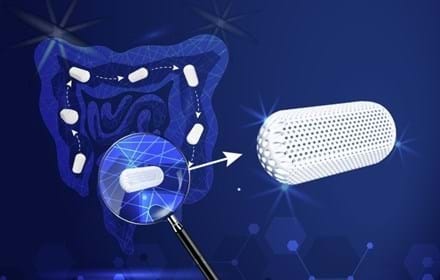

Första patienten i SHINE behandlas av SiPore21